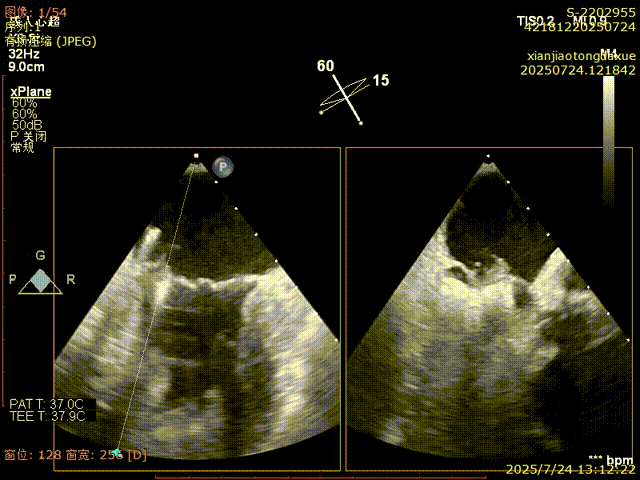

影像评估提示病变位于二尖瓣三区交界,瓣膜结构复杂,患者低氧血症,无法耐受体外循环,传统外科修复风险高,微创TEER治疗成为优选方案。手术团队采用ValveClamp® II型夹进行精准定位与夹合。通过麻醉快速通道迅速、高效完成手术,术中经经食道超声(TEE)实时引导,夹子精准落点于三区交界,瓣叶抓取稳定,夹合线条自然,反流显著改善,术后即刻拔除气管 ,插管,术后无并发症,心功能恢复良好。

确认夹合位置及效果

3D确认夹合位置